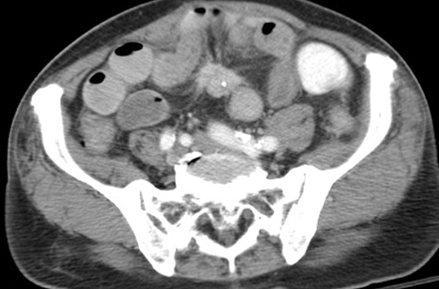

✨Up Next in our Member Spotlight Series - featuring Dr. Rocky Saenz! His passion for education has inspired numerous medical students and radiology residents. Dr. Saenz has made significant strides for DOs and radiologists, enhancing their recognition in the medical field.